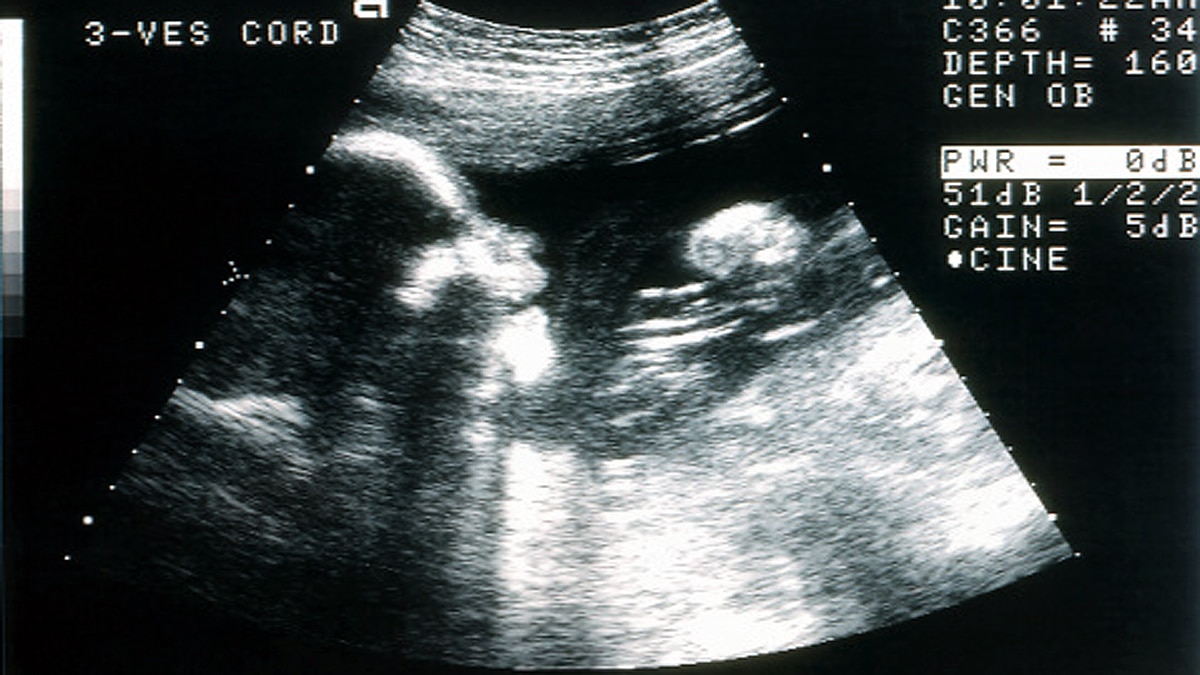

रीसलैंड का कहना है कि अगर गर्भ के अंदर बच्चों के एक्सप्रेशन की बारीकी से जांच की जाए तो हम डेवलपमेंटल डिसॉर्डर या अन्य स्वास्थ्य संबंधी दिक्कतें तो नहीं हैं. अगर सारे फेशियल एक्सप्रेशन सही आ रहे हैं तो उससे पता चलता है कि बच्चे का स्वास्थ्य गर्भ के अंदर सही है. बच्चे के चेहरे के एक्सप्रेशन बाहरी दुनिया में आने के बाद सामाजिक हो जाते हैं, लेकिन गर्भ के अंदर की भाव-भंगिमाएं उसके दर्द, सेहत या बेचैनी को दिखाती है. (फोटोः गेटी)